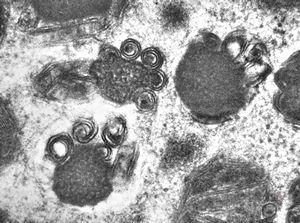

M,3y. | mast cell - granules with scroll-like formations - n. suralis, Krabbe globoid leukodystrophy

M,3y. | mast cell - granules with scroll-like formations - n. suralis, Krabbe globoid leukodystrophy

F,23y. | mast cell - granules with scroll-like formations - n. suralis, demyelinating neuropathy

F,31y. | mast cell - granules with scroll-like formations - n. suralis, demyelinating neuropathy

M,12y. | mast cell - granules with scroll-like formations - skin, urticaria pigmentosa